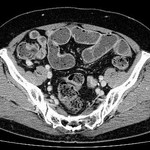

[画像診断]虫垂の粘液嚢腫(mucocele)について 2010-10-14